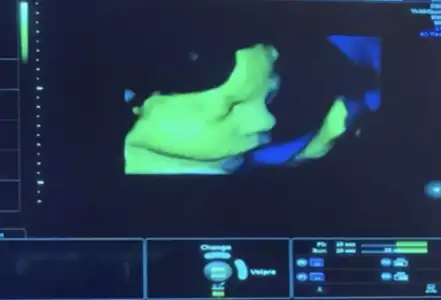

Kontrolden geldik kızlar oğlum 29+4 olmuş. Kilomuz da 1436 olmuş. Nasıl sizce iyi mi? Suyum fazlalaşmış. Şekeri az tüket dedi. Su üst sınıra gelmiş. Niye artar ki? Göğüs kalkanı gümüş kapak aldım ben de ilkinde avent silikon kalkan kullanmıştım ama benim göğüslerden yara olması yüzünden kan geliyordu ve 3 ay çektim. Ne lansinoh ne avent geçirmemişti. Gümüş kalkanı şimdi kullanıcam inşallah öyle yara olmaz yine. Şimdiden lansinoh sürmeye başladım çünkü şimdiden acımaya başladı benimkiler. İlkinde uçları çok küçüktü. Şimdi göğüs uçları var baya. Bakalım yara olayından çok korkuyorum. Oğluşumu da şöyle yandan çektik bi maşallahınızı alalım